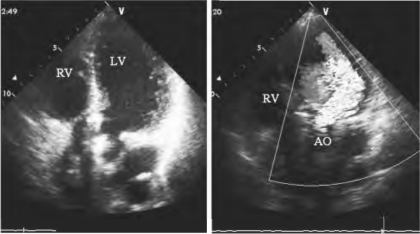

图13-23 人工瓣瓣周漏声像图(见彩图15)

左图为心尖五腔切面示主动脉位人工瓣环强回声及与二尖瓣环部之间裂隙,右图示舒张期彩色多普勒由此处进入左室的反流束